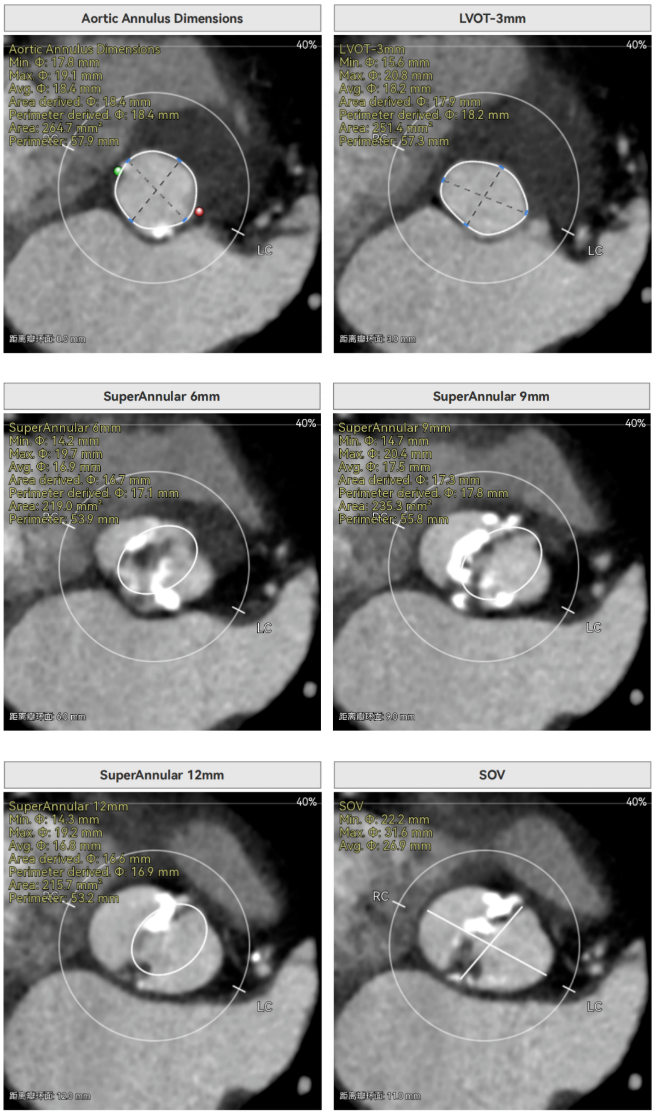

CT报告提示

主动脉瓣环周长径18.4mm,极小瓣环,LVOT直筒型结构;Type0型二叶瓣,鱼嘴处最窄预估宽度16.9mm。心脏角度34°,窦部空间大,无冠脉风险。

HU850钙化积分644,中重度钙化,瓣上限制较重,对瓣膜径向支撑力有一定要求,自杀左室,术前合并轻度反流,有一定循环崩溃风险。